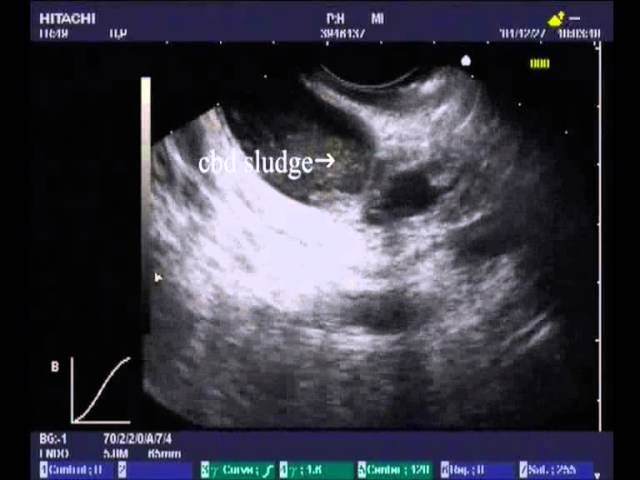

Пример: Женщина 65 лет с раком поджелудочной железы. На УЗИ в желчном пузыре определяется плотный камень — большое округлое гиперэхогенное образование с тенью позади. Рядом с камнем билиарный сладж — неоднородная гиперэхогенная взвесь. Эндоскопическое УЗИ — это прекрасный метод для определения камней желчного пузыря. Камень был удален при холецистэктомии. Авторы: William R. Brugge, M.D., Harvard Medical School, Massachusetts General Hospital.

Пример: Женщина 78 лет с неоперабельным раком поджелудочной железы. При эндоскопическом УЗИ определяется расширенный общий желчный проток и неоднородная гиперэхогенная взвесь. Это билиарный сладж. Авторы: William R. Brugge, M.D., Harvard Medical School, Massachusetts General Hospital). Смотри здесь.